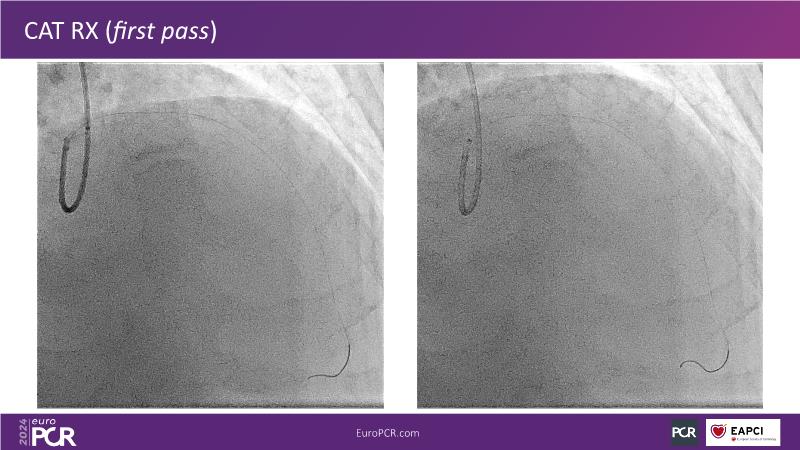

Tune into this 2024 session for insights into the latest ESC guidelines, strategies to prevent and treat no reflow, and an examination of trials like TASTE, TAPAS, and TOTAL on coronary thrombus management. Explore also the outcomes of the CHEETAH study, pondering a potential paradigm shift, and delve into a case study on thrombus removal in a patient with high thrombus burden.